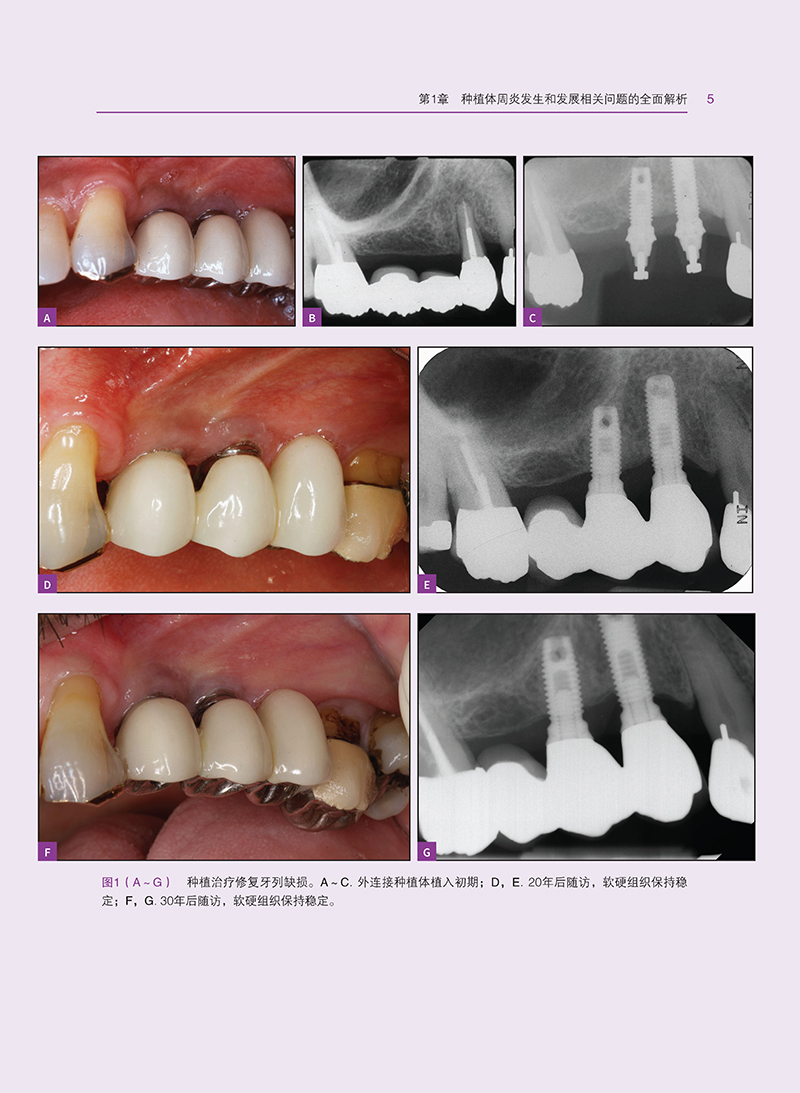

本书全面解析了种植体周炎的发生和发展相关问题,从诊断与监测到治疗策略,涵盖了种植体周炎的各个方面。首先,深入探讨了种植体周炎的形态学和表型特征,为读者提供了清晰的认识基础。接着,详细分析了种植体周炎的理想三维软组织和硬组织量,以及影响种植体周炎的局部风险因素、全身因素和不良习惯。同时,本书还介绍了遗传学和表观遗传学对种植体周炎的影响,为深入理解种植体周炎的发病机理提供了新的视角。